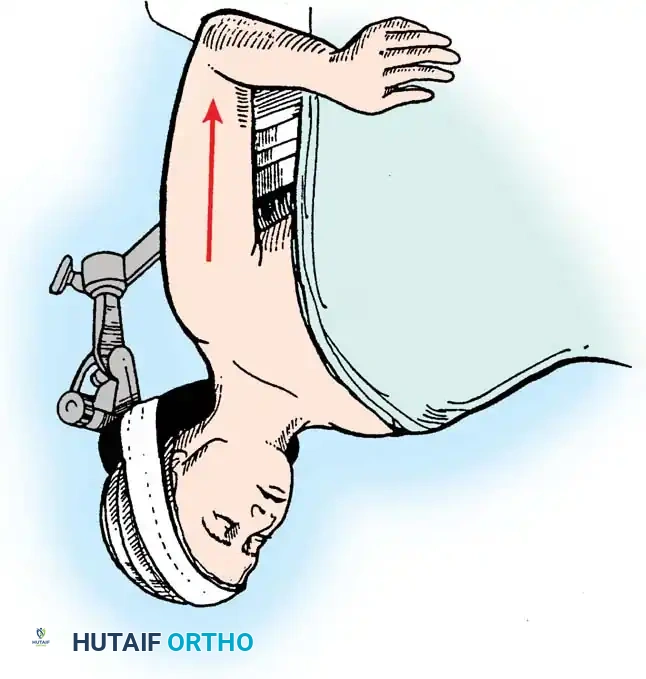

1. Positioning and Approach

The patient is placed in the lateral decubitus position with the arm draped over a bolster. A universal posterior approach is utilized.

- Ulnar Nerve Management: The ulnar nerve must be identified, mobilized, and protected throughout the procedure. Routine anterior transposition is performed at the conclusion of the case.

- Triceps Management: Several options exist, including a triceps-reflecting approach (Bryan-Morrey), a triceps-splitting approach, or a triceps-sparing approach. The Bryan-Morrey approach involves reflecting the triceps from medial to lateral in continuity with the anconeus and forearm fascia.